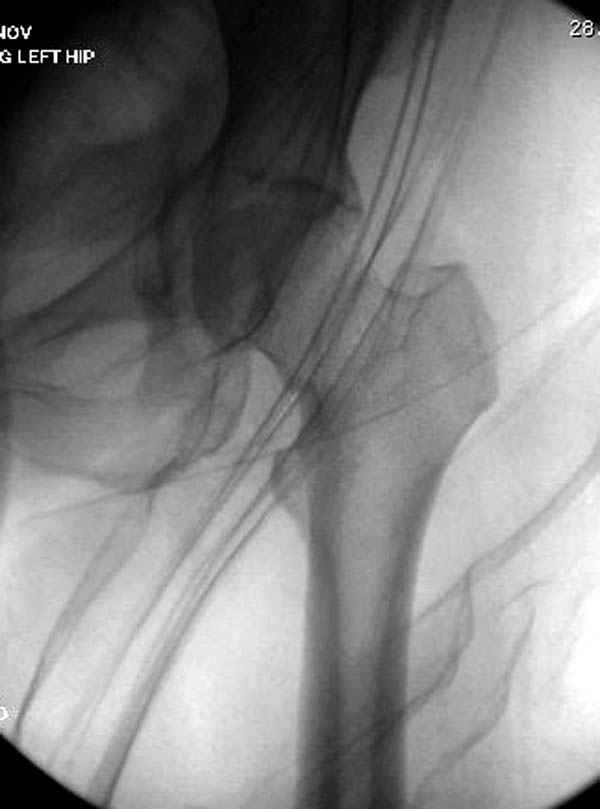

Долгое ожидание повышает риск АВН головки,

рекомендуется ургентная фиксация шейки в первые сутки, а в дальнейшем таз.

В данный момент скелетное вытяжение поучается через перелом шейки, а фиксированный перелом шейки будет участвовать в процессе вытяжения через каннюлированные шурупы.

Перелом шейки смогли зафиксировать через пару дней, ацетабулум до сих пор не оперирован, на вытяжении.

На снимке ацетабулума редко встречающийся очень низкий перелом, наверное, трудно было репозицию через один доступ? Перелом как бы замкнулся в квадрилатеральной поврехности.